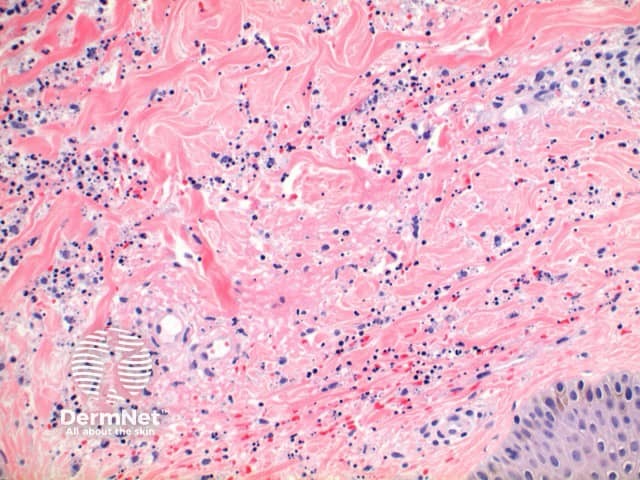

The histological features of leucocytoclastic (small vessel) vasculitis are:

Pathology of leucocytoclastic vasculitis